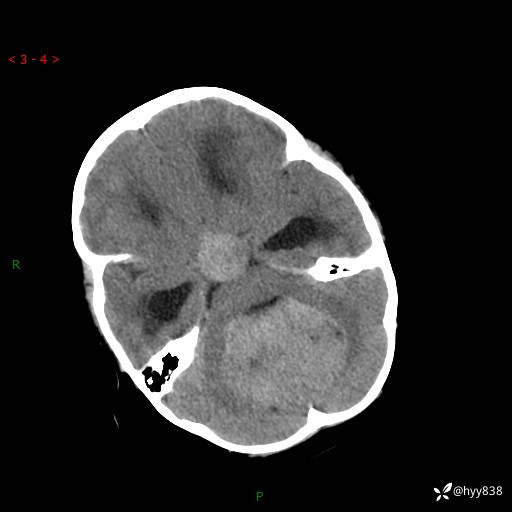

颅脑CT平扫

三脑室、四脑室多发病变,如何分析?

髓母细胞瘤 (13)